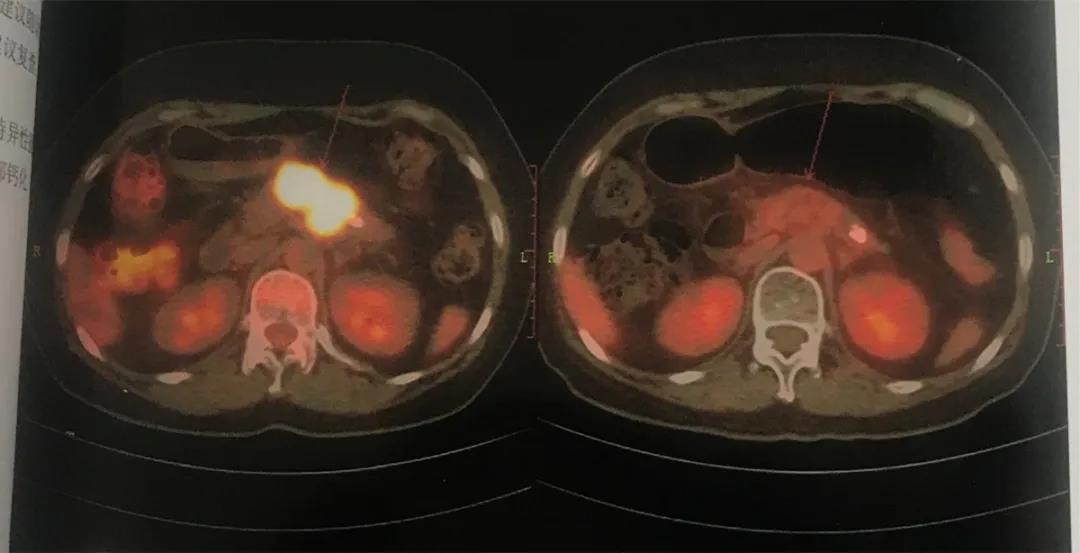

周莉胰腺癌放化疗后:原胰腺体部团块影现未见显示,局部未见FDG异常增高。(左排为2018.3.19pet/ct检查,右排为2019.8.21pet/ct检查)